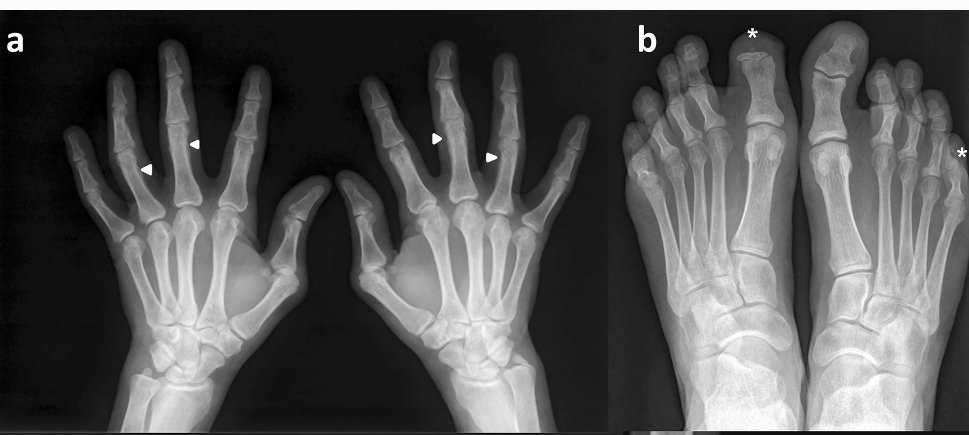

πŸ‘‰ characteristic patter of PsA is the coexistence of erosive changes and new bone formation as in this example where the same patient

πŸ‘‰(a, b) presented with fluffy periotitis in the proximal phalanges in both hands (arrow head)

πŸ‘‰ acro-osteolysis (*) in the distal phalanges of the first toe in the right foot and the fifth toe of the left foot